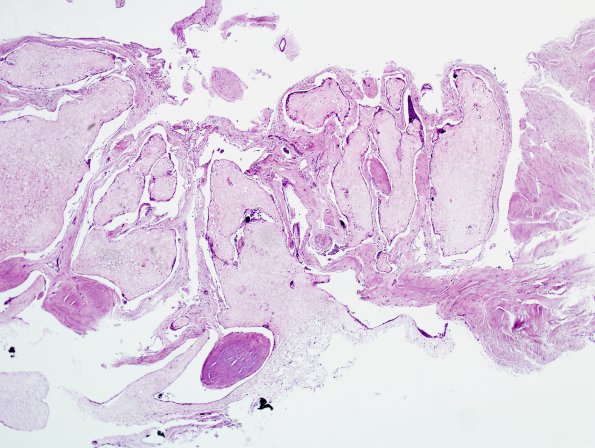

Washington University Experience | BASIC PROCESSES | Arachnoid villi - granulations | 15A1 Arachnoid granulations (Case 15) H&E 1

15A1,2 Numerous arachnoid villi are surrounded by arachnoidal cap cells, seen at higher magnification (#15A2) (H&E)